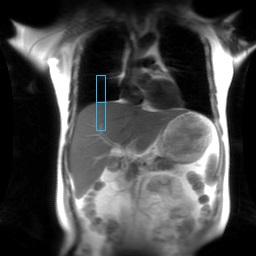

Figure 7. On the axial localizer, the tracker is placed in the middle of the liver in the anterior/posterior direction

- The tracker position is automatically placed on the localizer based on the Auto Tracker Placement post-processing application.